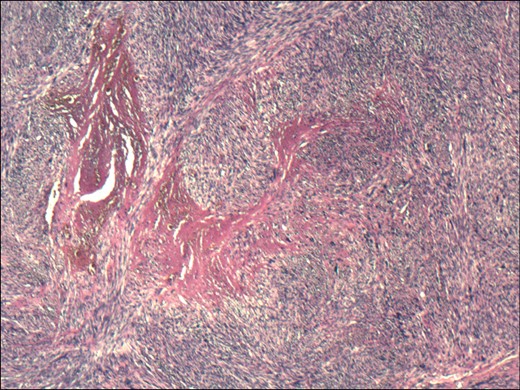

Haematoxylin and eosin stained section showing a spindle-celled tumour with pleomorphic nuclei and pronounced mitotic activity.

Morphologically, leiomyosarcoma is a spindle-celled tumour resembling a gastrointestinal stromal tumour. The two entities are best distinguished with immunochemistry with leiomyosarcomas positive for smooth muscle cell markers (smooth muscle actin, desmin, caldesmon) and negative for c-kit and DOG1, as in our case. The tools to definitively distinguish the two were only developed in the late 1990s [8]. Gastrointestinal leiomyosarcomas are exceedingly rare, with a recent literature review highlighting only 76 published cases, 30 of which were in the small bowel [9]. Ileum was the second most common site of the tumour in the small intestine after the duodenum.